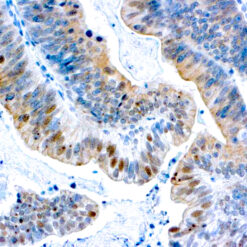

Leukocyte Common Antigen (LCA)/CD45

CD45R, also designated CD45 and PTPRC, has been identified as a transmembrane glycoprotein, broadly expressed among hematopoietic cells. Multiple isoforms of CD45R are distributed throughout the immune system according to cell type. These isoforms arise because of alternative splicing of exons 4, 5, and 6. The corresponding protein domains are characterized by the binding of monoclonal antibodies specific for CD45RA (exon 4), CD45RB (exon 5), CD45RC (exon 6) and CD45RO (exons 4 to 6 spliced out). The variation in these isoforms is localized to the extracellular domain of CD45R, while the intracellular domain is conserved. CD45R functions as a phosphor-tyrosine phosphatase. Antibody to CD45 is useful in differential diagnosis of lymphoid tumors from non-hematopoietic undifferentiated neoplasms.

| Cellular Localization | Cell membrane and Cytoplasmic |